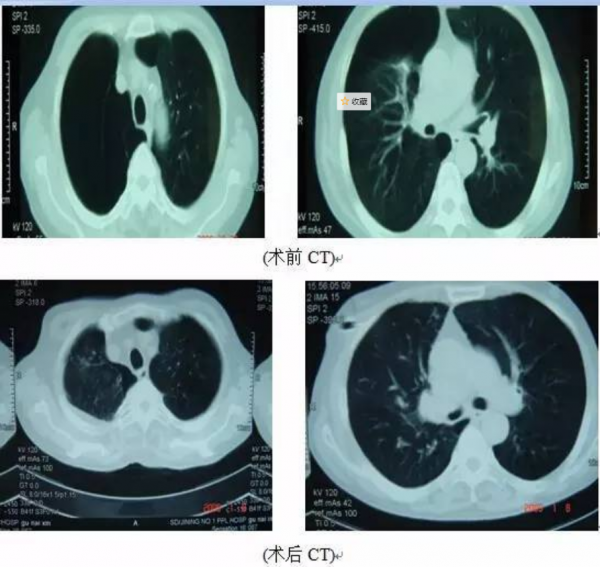

胸部CT顯示右側氣胸,雙肺肺氣腫

在全麻胸腔鏡下右肺大皰切除+肺減容術。手術順利,在胸腔鏡下用切割縫合器加墊片呈倒U型切除右上肺周邊20%氣腫肺組織及肺大皰。